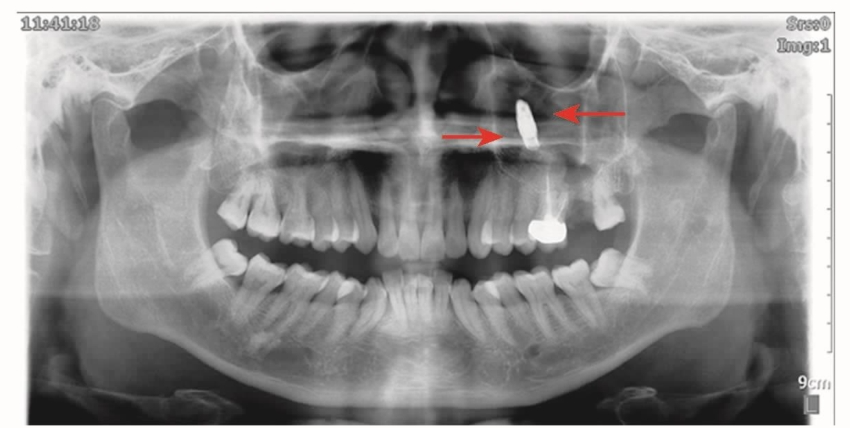

图3 全景片显示种植体位于左侧上颌窦内B56根尖上方

下牙槽神经管是下颌骨非常重要的结构,当下牙槽神经管损伤后会出现麻木或者其他的症状。误读全景片或者不了解全景片的失真率往往是造成手术意外的原因(图7)。

图7 全景片及CBCT冠状位A.全景片显示种植体压迫下牙槽神经管上壁;B.CBCT冠状位显示种植体进入下牙槽神经管内

对于全景片上神经管影像不清晰或者不能确定时,最好用CBCT检查,以确定神经管的位置,有没有其他分支,距离牙槽嵴的高度,颊舌侧的宽度以及有无颏孔舌侧开口等。在下颌骨骨量不足的情况下,种植手术时要高度警惕,尽量避免种植体进入下牙槽神经管(图8)。

图8 全景片显示C5、C6种植体进入下牙槽神经管

另外,过度追求种植体的长度也许是不科学和不明智的选择,损伤下牙槽神经管的风险是非常大的(图9)。

图9 全景片显示左侧D6种植体完全超过下牙槽神经管,D7种植体进入下牙槽神经管